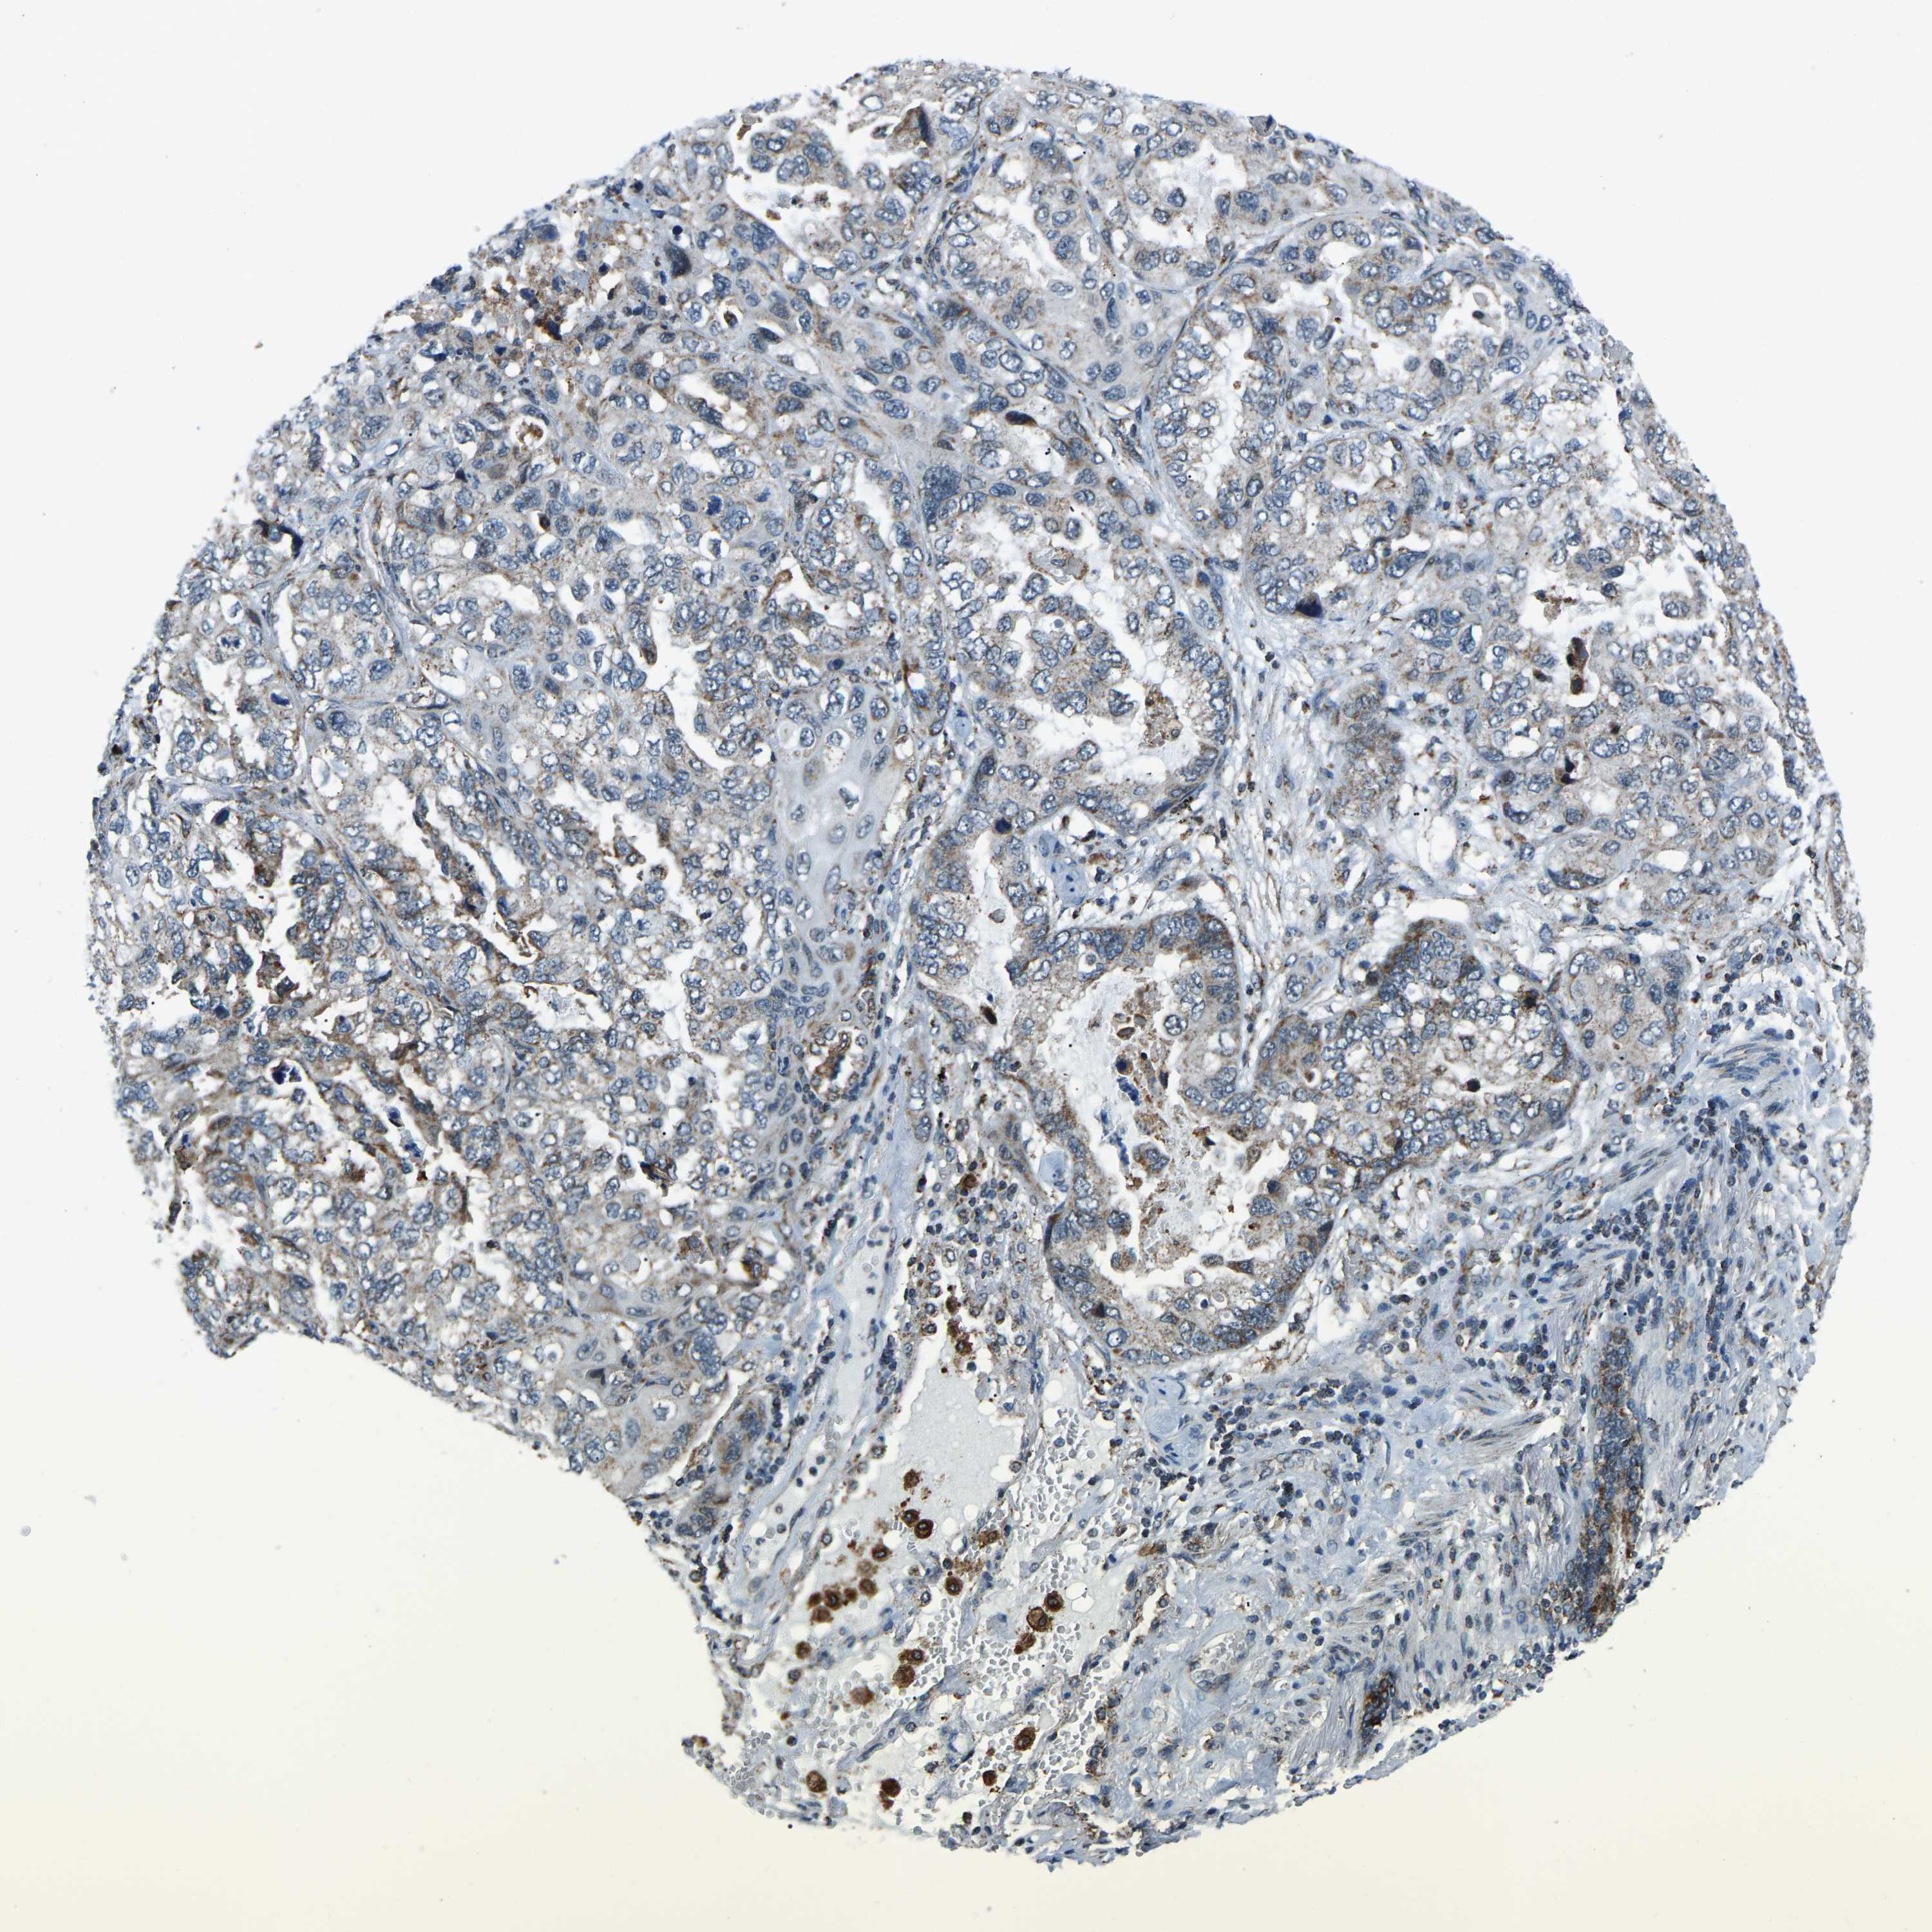

LUNG ADENOCARCINOMA (VALIDATION) - Interactive survival scatter ploti

The Survival Scatter plot shows the clinical status (i.e. dead or alive) for all individuals in the patient cohort, based on the same data that underlies the corresponding Kaplan-Meier plots. Patients that are alive at last time for follow-up are shown in blue and patients who have died during the study are shown in red.

The x-axis shows the expression levels (FPKM) of the investigated gene in the tumor tissue at the time of diagnosis. The y-axis shows the follow-up time after diagnosis (years). Both axes are complimented with kernel density curves demonstrating the data density over the axes. The top density plot shows the expression levels (FPKM) distribution among dead (red) and alive patients (blue). The right density plot shows the data density of the survived years of dead patients with high and low expression levels respectively, stratified using the cutoff indicated by the vertical dashed line through the Survival Scatter plot. This cutoff is automatically defined based on the FPKM cutoff that minimizes the p-score. The cutoff can be changed by dragging the vertical line or by entering a cutoff value in the square labeled "Current cut-off".

Under the Survival Scatter plot the p-score landscape (black curve; left axis) is shown together with dead median separation (red curve; right axis). Dead median separation is the difference in median mRNA expression between patients who have died with high and low expression, respectively. It is calculated as follows: median FPKM expression of dead patients with high expression - median FPKM expression of dead patients with low expression. This is intended to aid the user in visually exploring custom cutoffs and the associated p-scores and dead median separation.

Individual patient data is displayed and can be filtered by clicking on one or more of the category buttons on the top of the page. Categories describing expression level and patient information include: high, low, alive, dead, female, male and tumor stages. The scale of the x-axis can be toggled between linear and log-scale by clicking on the "x log" button. Mouse-over function shows TCGA ID, patient information and mRNA expression (FPKM) for each patient.

& Survival analysisi

Kaplan-Meier plots summarize results from analysis of correlation between mRNA expression level and patient survival. Patients were divided based on level of expression into one of the two groups "low" (under cut off) or "high" (over cut off). X-axis shows time for survival (years) and y-axis shows the probability of survival, where 1.0 corresponds to 100 percent.

RBM33 is not prognostic in Lung Adenocarcinoma (validation)

: 15.5